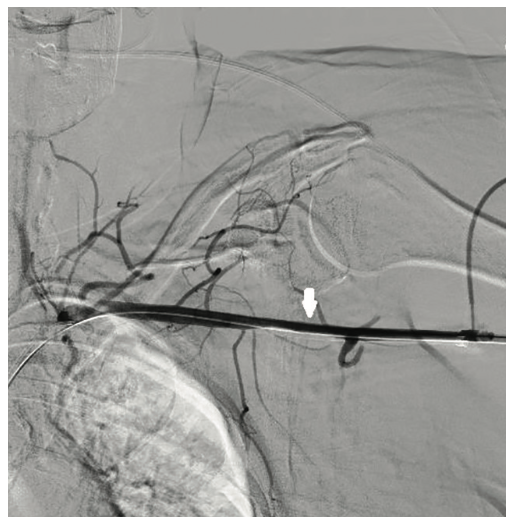

The right groin was accessed using fluoroscopic guidance. A micropuncture sheath was placed and upsized to a 7 French, 45 cm Destination sheath (Terumo) in the right groin. We accessed the right radial, but could not get good flow. Therefore, we ended up using the ulnar artery with ultrasound guidance and placed a Terumo 5/6 Slender sheath in the ulnar artery. We proceeded to access the left axillary artery. We placed a Judkins right (JR)4 catheter in the left subclavian and did a selective angiogram, documenting the location of the thoracoacromial artery and circumflex humeral (Figure 4); then using a Chiba biopsy needle (Cook), accessed the axillary artery and placed a 5-French 30 cm sheath (Cook)(Figure 5). We used the 15 cm biopsy needle to allow us a shallow angle of approach with the patient’s body habitus and to avoid “kinking” the sheath. We then switched out for the Lunderquist wire (Cook Medical), placed an 8 Fr sheath, and performed a pre-close using two Perclose devices (Abbott Vascular) (Figure 6).

Ideally, the axillary artery should be accessed in the second portion, which runs behind the pectoralis minor muscle. This is clinically important, since it is associated with the lowest chance of causing brachial plexus injury. These landmarks are often seen using ultrasound imaging. However, our practice is to use selective angiogram of the subclavian and axillary arteries. Once the axillary artery and all branches are defined, the access point should be lateral to the thoracoacromial artery and medial to the circumflex humeral arteries (Figures 22-23). We recommend a shallow angle of approach, since the Impella sheath is prone to kinking; alternatively, a Cook 14 Fr x 13 cm sheath can be used for the Impella 2.5 or a Cook 14 Fr x 30 cm sheath for the Impella CP.

- Angiographic assessment of the axillary artery and all branches is an important step to define an access point that is lateral to the thoracoacromial artery and medial to the circumflex humeral artery (Figures 22-23).